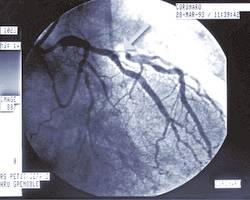

La coronarographie est un examen radiologique (rayons X) qui consiste à opacifier les artères du cœur afin de les visualiser. Cet examen très spécialisé n’est indiqué que pour des cas (...)